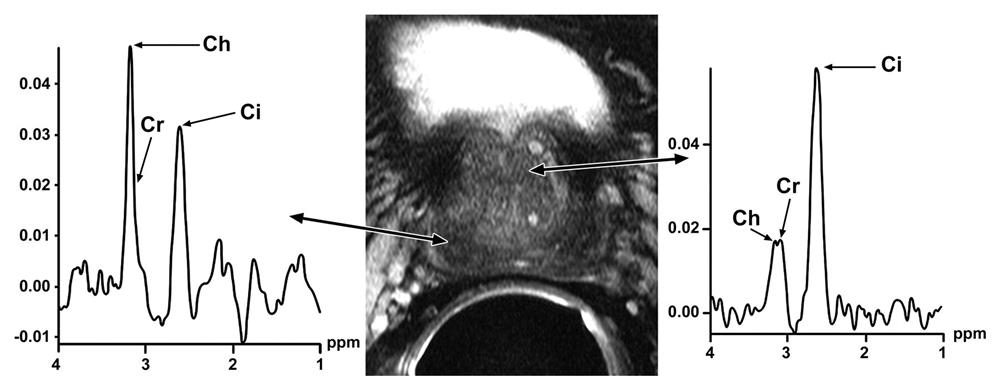

Hình ảnh quang phổ có thể hữu ích để đánh giá nguy cơ ác tính của một khu vực quan tâm (ROI), nhưng nó ít hữu ích hơn trong việc xác định bệnh ác tính và dự đoán giai đoạn bệnh lý. Quan sát chính là các tế bào ác tính có nhiều khả năng có tốc độ di chuyển tế bào nhanh, do đó sẽ sử dụng nhiều kẽm hơn và giảm trong không gian nội bào [6].

Trong ung thư tuyến tiền liệt, đỉnh citrate giảm (do tiêu thụ citrate để cung cấp năng lượng cho các tế bào tăng sinh), trong khi đỉnh choline tăng (tương ứng với tổng hợp màng tế bào tăng).

Bệnh nhân B.N.P ung thư tiền liệt tuyến vớiMRS đỉnh Choline cao, Citrate thấp. DCE tại 2 điểm nghi ngờ với curve type 2+ 3.

Bệnh nhân N.T.B ung thư tiền liệt tuyến vớiMRS đỉnh Choline cao, Citrate thấp. DCE Curve type 3.